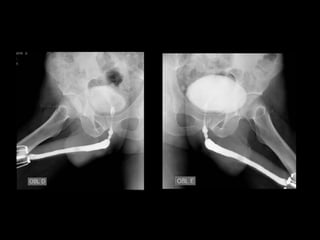

Sequência do exame

Radiografia simples AP - filme 24x30

Radiografia oblíqua D e E - filme 35x35

Radiografia de pequeno enchimento vesical – filme 24x30

Radiografia de médio enchimento vesical – filme 24x30

Radiografia de grande enchimento vesical – filme 24x30

Pesquisa de refluxo vesicoureteral - 35x43

Radiografia durante micção AP – filme 35x35

Radiografia durante micção oblíqua D – filme 35x35

Radiografia pós-micção – filme 24x30.

Sequência do exame:

 Posição em AP

 Passar a sonda vesical;

 Injeção do meio de contraste;

 Radiografia de pequeno enchimento vesical – filme 24x30;

 Radiografia de médio enchimento vesical – filme 24x30;

 Radiografia de grande enchimento vesical – filme 24x30;

 Pesquisa de refluxo vesicoureteral - 35x43

 Radiografia miccional AP - 35x35

 Radiografia miccional Oblíqua -35x35

 Radiografia pós- micional -24x30